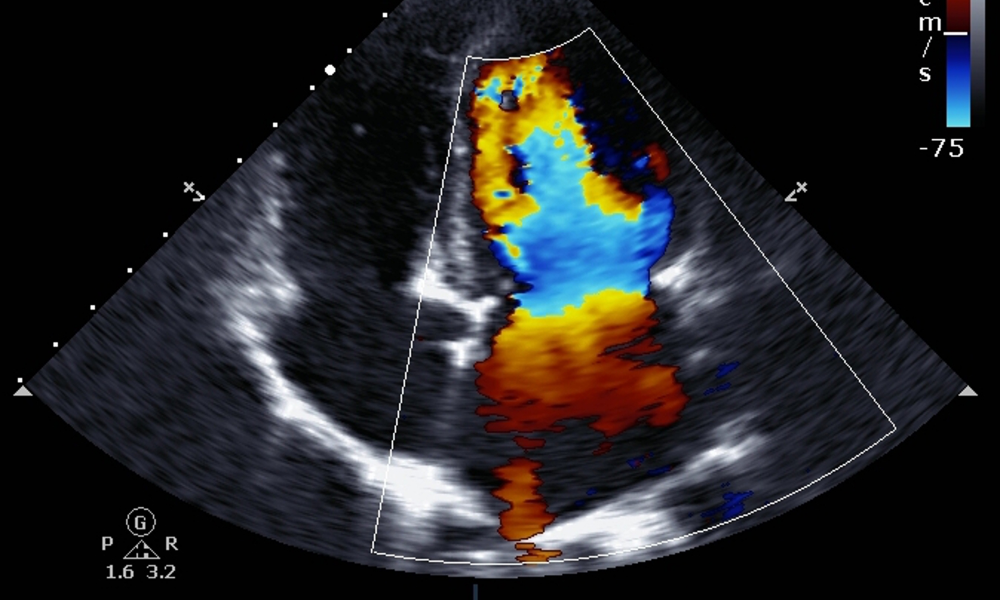

At Das Hospital in Chembur, our Color Doppler service helps you understand how well blood flows through your arteries and veins using a simple, non-invasive test. This advanced ultrasound-based scan shows real-time blood movement, detects blockages or narrowing, and supports early diagnosis of conditions like DVT, carotid artery disease, and other vascular problems. It is also an important part of pregnancy care, helping monitor the placenta, umbilical cord, and fetal wellbeing with complete safety.

Our radiology team uses high-resolution Doppler systems to deliver fast, clear, and reliable results so your doctor can make timely decisions about your treatment. The test is painless, radiation-free, and suitable for people of all ages, including expecting mothers. Whether you need vascular screening or prenatal monitoring, Das Hospital provides accurate imaging and expert interpretation to support better health outcomes.